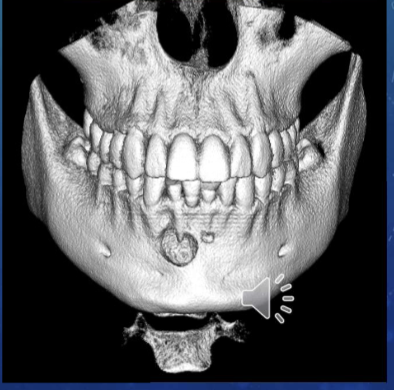

CBCT scan - cone beam, computed tomography

spatial res - voxels 3-dimensional pixels

unable to assess from this single image the objects buccal-lingual position relative to the teeth

volumetric rendering

commons uses of 3D imaging

improved interpretation diagnosis and treatment planning of dental care

implant placement

extraction or exposure of impacted teeth

definition of anatomic structures